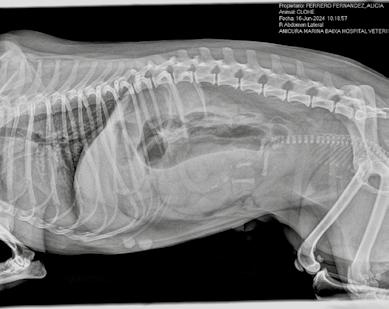

2. Radiografía de abdomen

El objetivo es valorar el tamaño y posición fetal y descartar obstrucciones en el canal del parto. También se puede contabilizar el número de fetos. Para ello, es más fiable contar el número de cabezas. Normalmente se visualiza mejor en una proyección VD. Figura 2.

Figura 2. RX de hembra gestante con medidas de cabeza y canal pélvico.